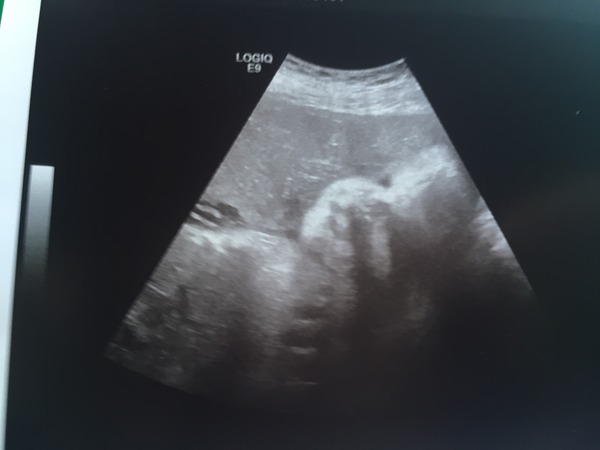

Well bump is a offically head down and everything is well out of the way and where it should be. Still definantly team blue too!

Scan looked just as alien like as I remember with dd at such a late stage. Was given a picture of him cuddled up to the plancenta, and can just about make out top lip, nose and eye. His on the left looking very comfortable, placenta on the right. Estemated to be 5lbs11ozs today.

Dobby Great news about the scan, the picture is adorable, his nose is too cute Smile

Dobbie glad everything went ok.. It took me a minute of magic eye squinting there to find him! The weights the rest of you are coming back with from your scans are starting to reassure me a bit more that I'm not so far out like the consultant made out! She turned away from cuddling the placenta to give us a thumbs up or the finger depending on how you look at it